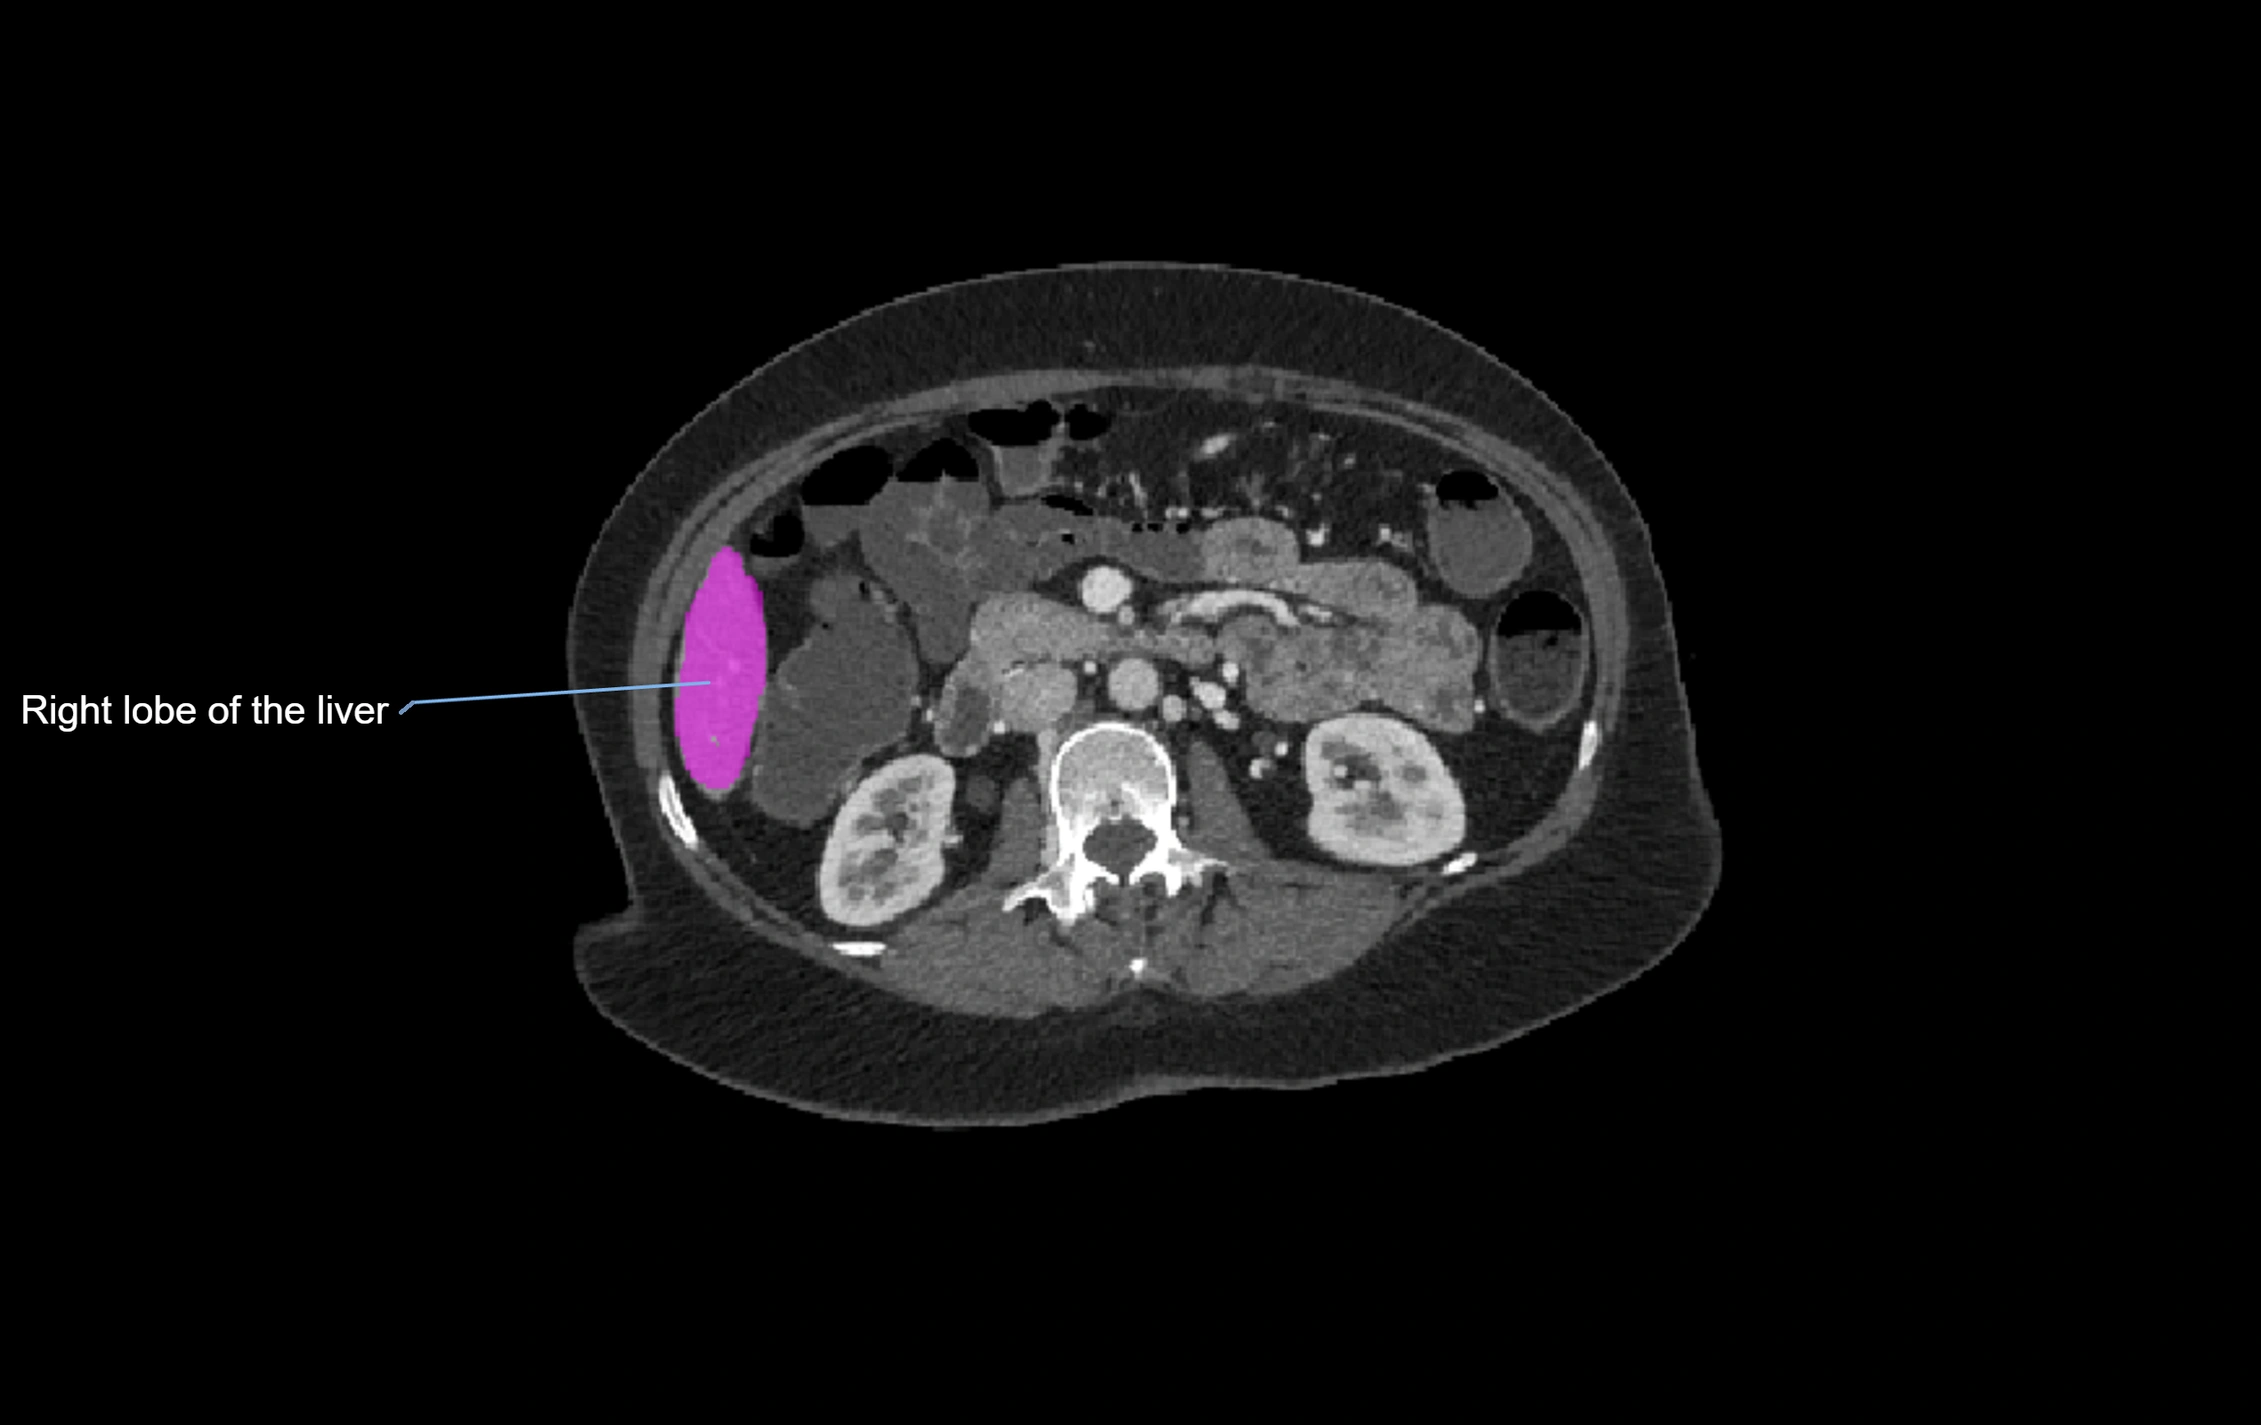

CT Image

image